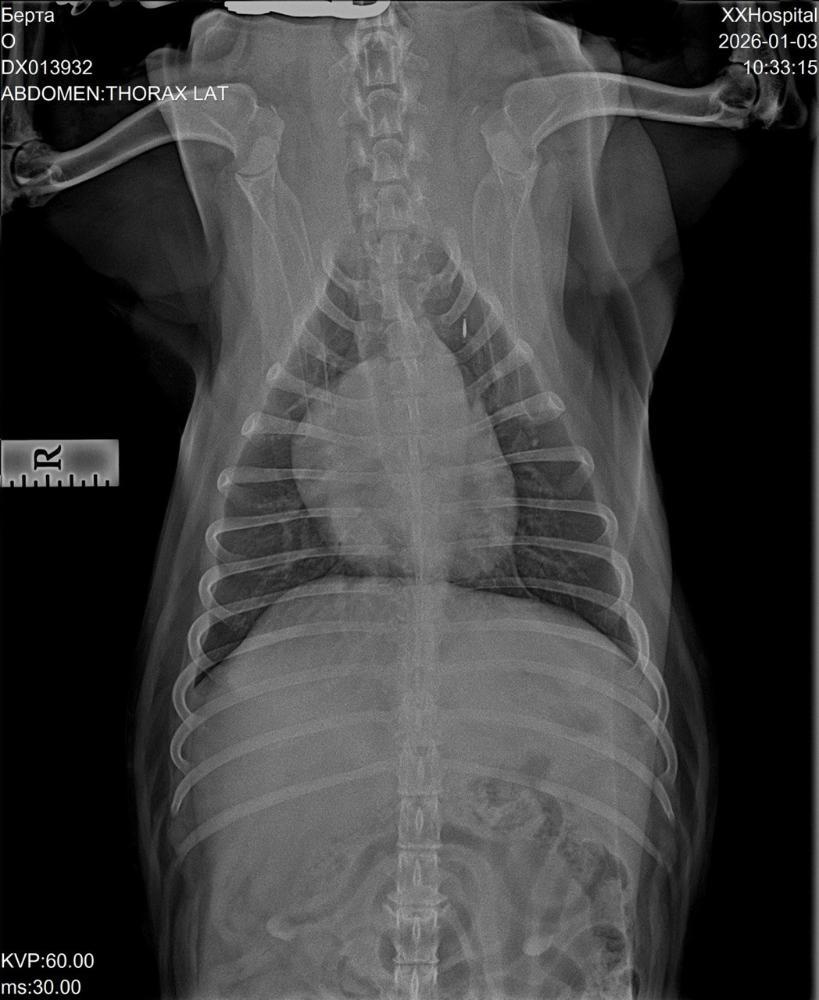

Вячеславовна Опубликовано 3 января Автор Опубликовано 3 января Добрый вечер!!! С'ездили сегодня с Бертой к кардиологу и пульманологу. По сердцу: расшифровка холтера неплохая, отменили ветмедин, через полгода пройти кардио обследование. Сдали ОКА и биохимию. Сделали рентген. ( результаты на почту). Тот кашель, который есть сейчас, не сердечный. Для диагностики кашля рекомендована ларинготрахеобронхоскопия(исключить изменение гортани, в тч ретро версию надгортанника, частичный паралич) и БАЛ. Всё это удовольствие на вес Берты стоит 30000р.🤔🧐🤔🧐 Подбор терапии по результатам обследования. Сейчас бромгексин 8 мг и ингаляции с физ раствором. Финансовый отчёт. Остаток: 15590р. Расходы: Пульманологу, рентген, анализы -8853р. Зоотакси -1330р. Остаток: 5407р. Помощь Берте очень актуальна!!! Мой номер 89261818009 привязан к карте СБ на имя Марина Вячеславовна М. с пометкой " Берта". 1